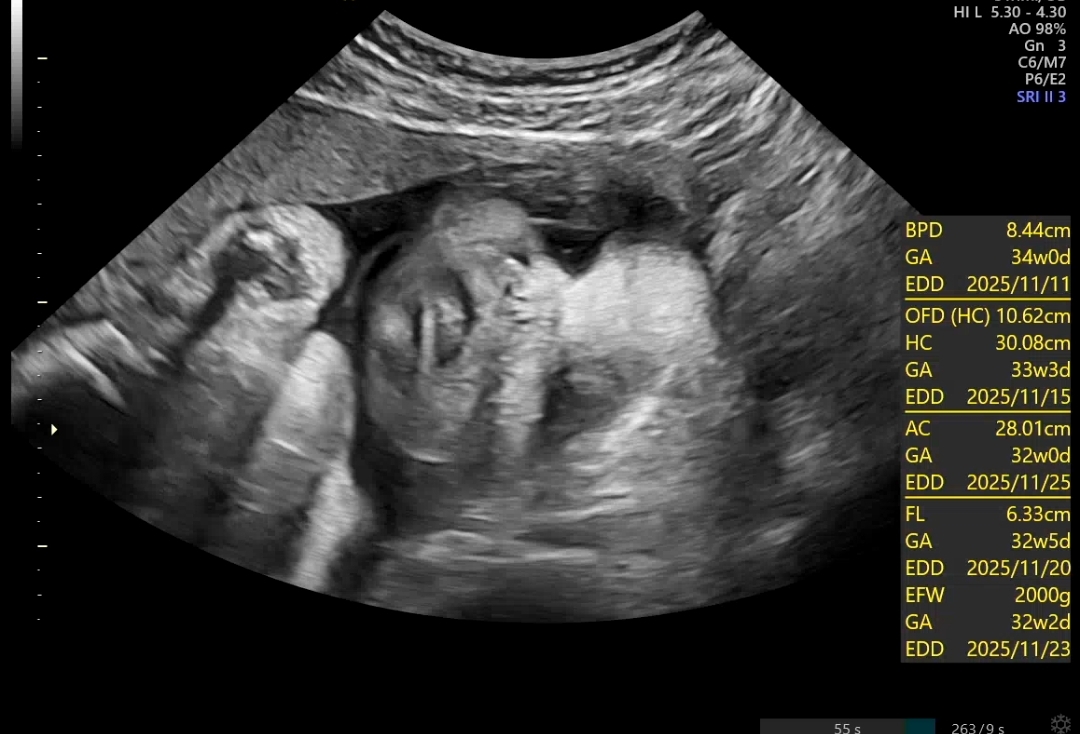

임신 32주 4일. 이제 정말 출산이 가까워졌다는 사실이 하루하루 더 크게 다가온다. 저번 주까지만 해도 입원 치료를 마치고 퇴원할 때 자궁경부 길이가 2.5cm 정도로 유지되고 있었다. 그때는 의사 선생님이 “아직은 괜찮다”라는 말을 해주셔서 마음을 놓았는데, 일주일 만에 외래 진료를 갔더니 수치가 또 달라져 있었다. 이번에는 1.8~1.5cm. 짧아졌다는 얘기를 듣는 순간, 심장이 덜컥 내려앉았다.

아주 잘크고 있는 만세 2키로 돌파..!!